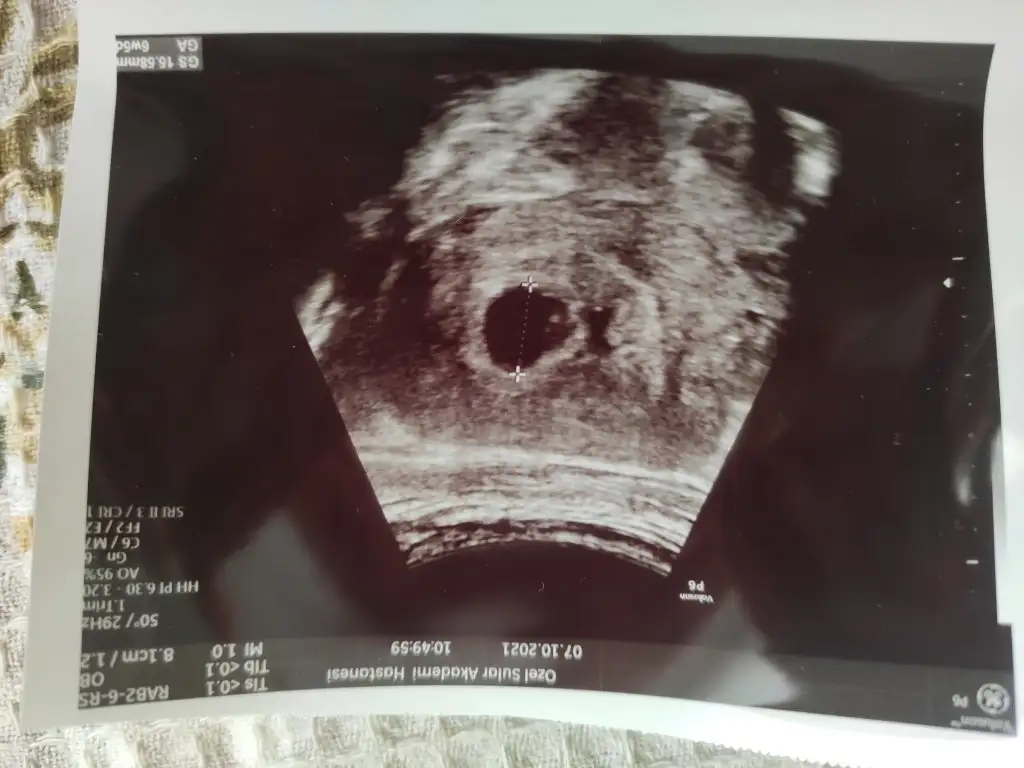

Pozitif konuştuysa süper canım ama anlamadığım önce deneseymiş duymayınca 2 hafta sonraya çağırsaymış bence 10 gün sonra duyulur çok rahat sen kontrol gününde git uyanıklık mı yapıyor ne doktorun sen de uyanıklık yapSelam kızlar geldim hastaneden, maalesef biraz hayal kırıklığı var kalp atışı dinletmedi. Kese ve bebek var kalp atışı için 15 gün sonra gel dedi, hocam bu haftalarda duyulması gerekmez mi dedim yok henüz duyulmaz dedi. Ama arkadaşlar duymuş dedim, herkesin döllenme zamanı farklıdır dedi, ama ben ovulasyon takibi yaptım hocam dedim, artık ters ters bakmaya başlayınca sustumkadın herşey gayet normal dedi pozitif konuştu ama benim moralim bozuk tabi, o kadar bekledim kontrol süresi 10 günmüş hastanede, 15 gün sonra tekrar gidip tekrar muayene ücreti ödeyecem bir de neyse en azından dış gebelik falan değil ama işte ne yapalım

Olsunn yinede çok şükür ki herşey yolunda canımSelam kızlar geldim hastaneden, maalesef biraz hayal kırıklığı var kalp atışı dinletmedi. Kese ve bebek var kalp atışı için 15 gün sonra gel dedi, hocam bu haftalarda duyulması gerekmez mi dedim yok henüz duyulmaz dedi. Ama arkadaşlar duymuş dedim, herkesin döllenme zamanı farklıdır dedi, ama ben ovulasyon takibi yaptım hocam dedim, artık ters ters bakmaya başlayınca sustumkadın herşey gayet normal dedi pozitif konuştu ama benim moralim bozuk tabi, o kadar bekledim kontrol süresi 10 günmüş hastanede, 15 gün sonra tekrar gidip tekrar muayene ücreti ödeyecem bir de neyse en azından dış gebelik falan değil ama işte ne yapalım